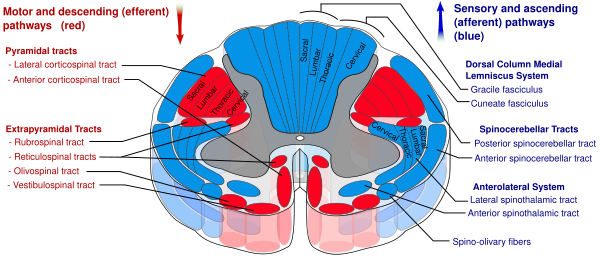

Восходящие нервные пути, соединяющие спинной мозг с таламусом, образуют спиноталамический путь, или спиноталамический тракт. В нём от спинного мозга к таламусу передаётся сенсорная информация о болевых, температурных и тактильных ощущениях, а также об ощущении зуда[14]. Спиноталамический путь подразделяется на две части: боковой, или латеральный, или дорсальный, спиноталамический путь[15], который передаёт информацию о болевых и температурных ощущениях, и передний, или вентральный, спиноталамический путь[16], который передаёт ощущения грубого прикосновения или сдавливания, надавливания[8].

В свою очередь, в боковом спиноталамическом пути выделяют эволюционно более молодой неоспиноталамический путь и более древний палеоспиноталамический путь. Первый состоит из большого количества тонких нервных волокон, которые быстро проводят болевые ощущения, а второй содержит меньшее количество более толстых и более медленно проводящих нервных волокон. Быстро проводящий неоспиноталамический путь играет большую роль в передаче в мозг хорошо локализованного ощущения острой боли непосредственно или вскоре после травмы, повреждения тканей, и в принятии организмом защитных мер, таких, например, как отдёргивание руки от горячего предмета. Более медленно проводящий палеоспиноталамический путь передаёт менее локализованную, более разлитую, тупую, давящую или сжимающую, реже жгучую или сверлящую хроническую боль, и играет большую роль в патогенезе различных хронических болевых синдромов[17][18].